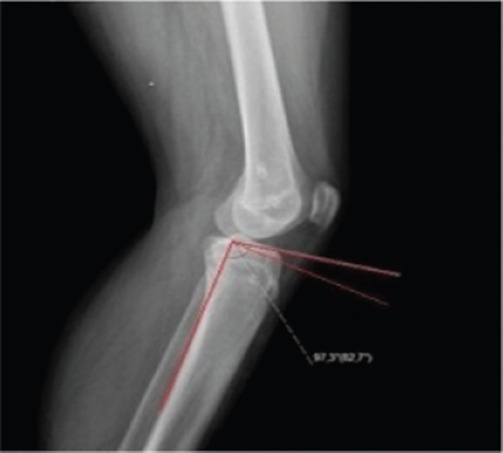

Objective: The aims of this study were (1) to investigate the tibial slope (TS) changes following guided growth by the eight-plate and to determine the relationship between the TS change in the sagittal plane and the plate position.

Methods: In this retrospective study, children who underwent guided growth by the eight-plate for genu varum or valgum were included. Thirty-eight extremities of 23 children (14 girls and 9 boys; mean age = 9.2 years, age range = 3-17 years) were then divided into two groups according to the plate location in the sagittal plane (anterior or midline). Preoperative and postoperative TS were measured from the medial and lateral tibial plateaus separately.